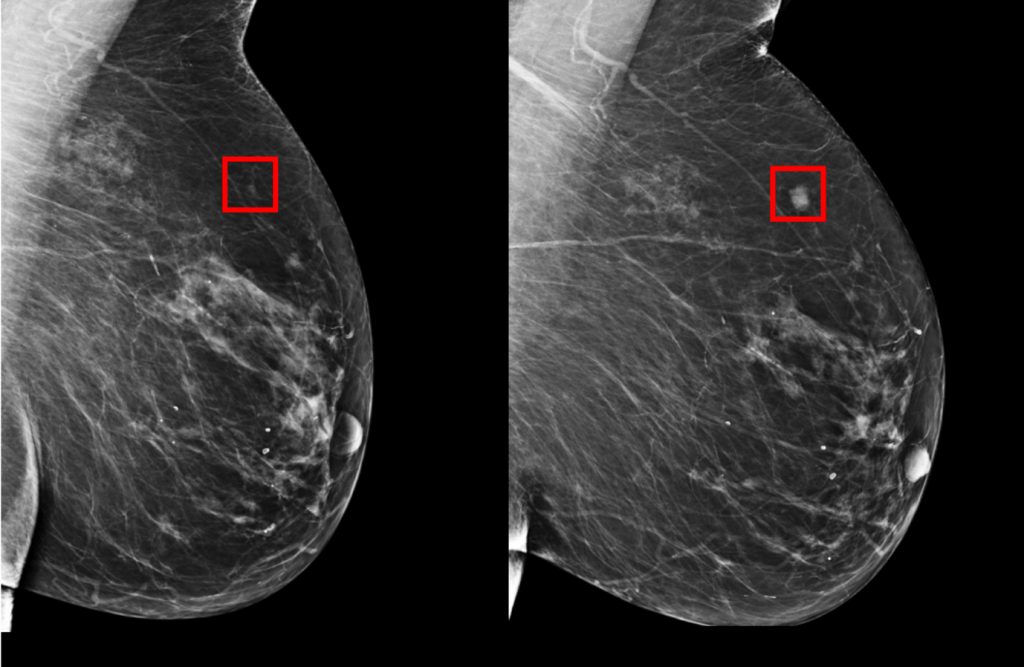

MIT AI tool can predict breast cancer up to 5 years early, works equally well for white and black patients

This MIT tool, which is trained on mammograms and patient outcomes (eventual development of cancer being the key one) from over 60,000 patients (with over 90,000 mammograms total) from the Massachusetts General Hospital, starts from the data and uses deep learning to identify patterns that would not be apparent or even observable by human clinicians. Because it’s not based on existing assumptions or received knowledge about risk factors, which are at best a suggestive framework, the results have so far shown to be far more accurate, especially at predictive, pre-diagnosis discovery.